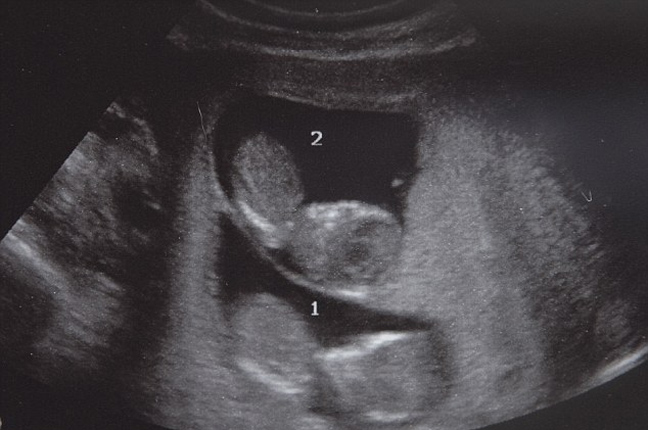

Για τους περισσότερους γονείς οι πρώτες φάσεις της ανάπτυξης του εμβρύου παραμένουν μυστήριο. Η πρώτη εικόνα που έχουν είναι στον υπέρηχο περίπου στις 12 εβδομάδες της κύησης.

Η Rachel και ο Dave Fisher ωστόσο δεν χρειάστηκε να περιμένουν τόσο για να «συναντήσουν» για πρώτη φορά τους δίδυμους γιους τους Max και Theo. Την πρώτη φορά που τους είδαν, μετά τη διαδικασία τεχνητής γονιμοποίησης, ήταν μόνο… κύτταρα.

Σήμερα τα αγόρια είναι δύο εβδομάδων και οι γονείς τους είχαν την ευκαιρία, χάρη στην τεχνολογία, να παρακολουθήσουν τις πρώτες τους ώρες στη ζωή.